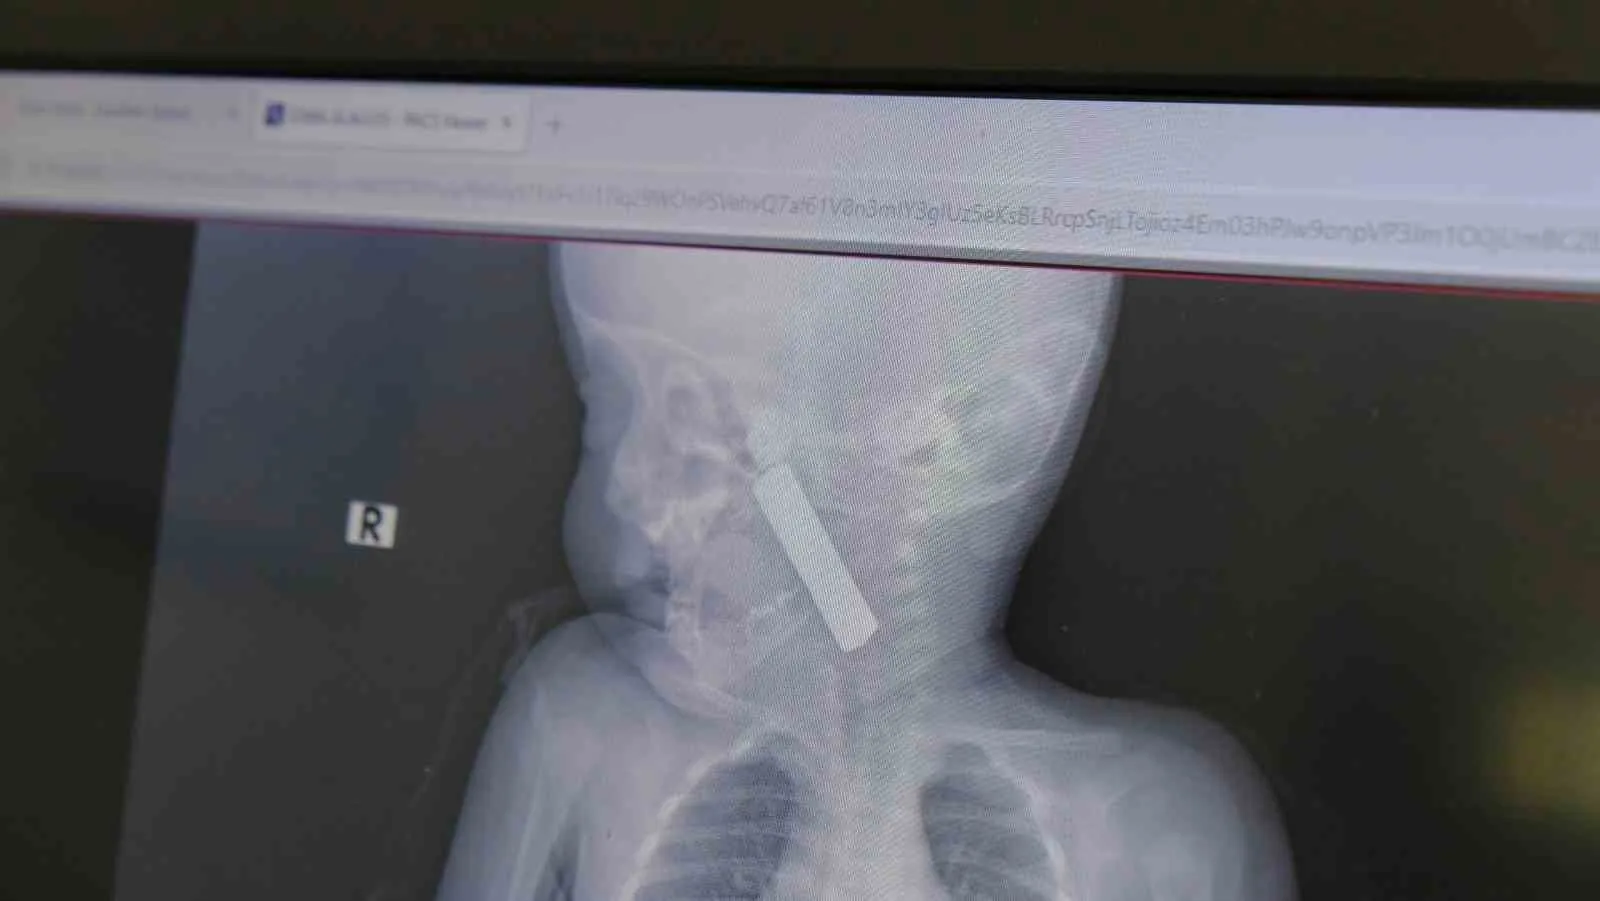

Karaman’da 6 aylık bebeğin boğazına kaçan kumanda pili, ameliyatla çıkarıldı. Edinilen bilgiye göre, kusma şikayeti ile ailesi tarafından Karaman Eğitim ve Araştırma Hastanesi acil servisine getirilen 6 aylık E.A. isimli kız bebeğin, yapılan muayene ve tetkiklerde boğazında kumanda pili kaçtığı tespit edildi. Solunum sıkıntısı da yaşayan bebek hemen ameliyata alındı. Çocuk Cerrahisi Uzmanı Doç. Dr. Mehmet Uysal tarafından yapılan ameliyatla bebeğin boğazındaki pil çıkarıldı. "Hemen müdahale ettik" Yaşanan olayla ilgili bilgi veren Doç. Dr. Mehmet Uysal, "Acil polikliniğimize kusma şikayeti ile 6 aylık bir kız bebek getirilmiş ve bize haber verildi. Biz de vakit kaybetmeden geldik, hastamızı gördük. Yapılan tetkikler sonucunda, ağız tabanına oturan ve yemek borusunun birinci darlığına kadar uzanan, kumanda pili dediğimiz bir pille karşılaştık. Filmde ve muayenede bunu gördük. Hastayı ilk gördüğümüzde bayağı siyanotik durumda, solunum sıkıntılıydı ve oksijen satürasyonu 90 civarındaydı. Böyle olunca bir an önce beklemeden hızlı bir şekilde ameliyathaneye götürdük. Orada ameliyathanedeki anestezi uzmanlarımız ve personel bize yardımcı oldu, hasta hızlı bir şekilde entübe edildi. Ondan sonra da laringoskop ve magill forseps dediğimiz malzemelerimizle bu yabancı cismi çıkarmış olduk. Bir an evvel müdahale ettik, iyi ki müdahale ettik, orada ağız tabanında, özellikle ön kısmında hasar oluşmuştu. Müdahale sonrasında da hastanın solunum problemleri bir süre devam etti, bu yüzden 24 saat takip ettik. Herhangi bir problem oluşmayınca 24 saat sonra kontrole gelmek üzere hastayı taburcu ettik" diye konuştu. "Aileleri uyarıyoruz" Ailelere uyarılarda bulunan Doç. Dr. Uysal, "Bu konularda aileleri uyarıyoruz. 1 yaş altı çocuklarda bile bu durum oluşabilir. Bazen 2-3 yaş diyoruz ama 1 yaş altındaki çocuklarda da emekleme döneminde bile bu tür yabancı cisimleri, özellikle kumanda pili, kalem pil gibi şeyleri ortada bırakmamak lazım. Çocuklar meraklı olduğu için her şeyi ağzına götürmeye meyilli. Dikkat etmediğimiz takdirde ölümcül sonuçlar oluşabiliyor. Bu vakada şanslıydık, çocuktaki durum erken fark edildi ve hemen müdahale edildi. Şu anda çocuk sağlıklı bir şekilde hayatına devam ediyor" dedi.